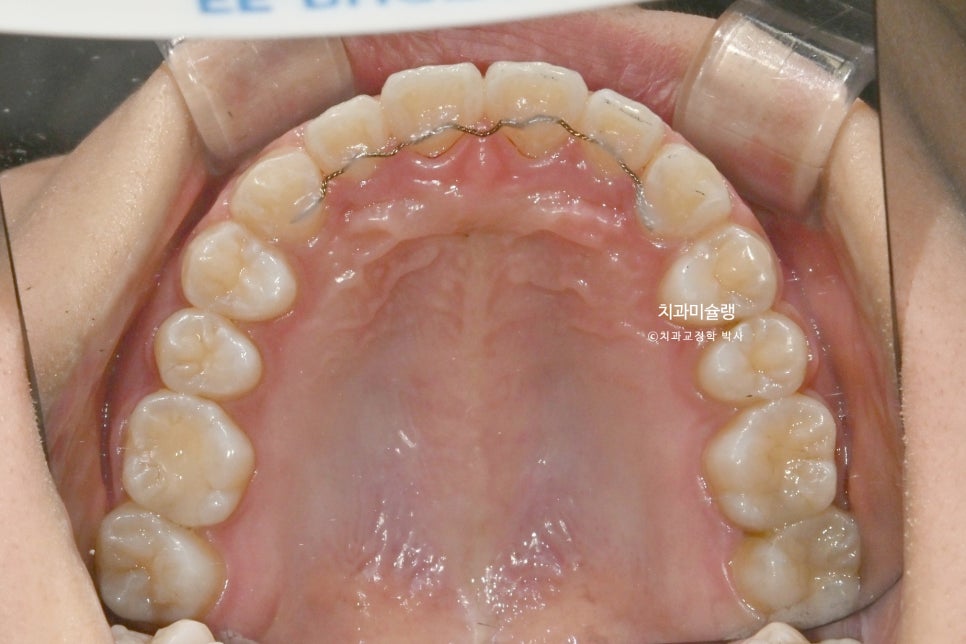

교정 치료 1년째 진행상황

클리피씨 교정 1년째 모습입니다.

상악엔 좌우 2개씩 총 4개, 하악에 좌우 1개씩 총 2개의 미니스크류를 심고 치료를 합니다.